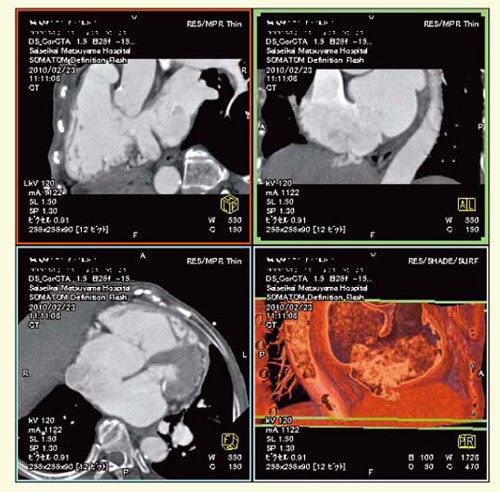

● 症例1:心房中隔欠損の術前評価

非常に大きな心房中隔欠損による心不全症例の術前検査として,経食道エコーとの比較を目的に心臓CTを撮影した(図4)。非常に鮮明な画像が得られ,かつVR像は360度回転して見ることができるため,心臓外科医から高く評価された。

図4 症例1:心房中隔欠損の術前評価

● 症例2:弁置換術後の評価

図5は弁置換術後のDefinition Flashによる心臓CT画像である。再手術を行った症例だが,弁の動きや角度,周囲の動脈硬化の程度などを判定するのにCTが非常に有効だった。Definition Flashの4Dシネ画像で弁の部分のみを取り出し,拡張期と収縮期で動きを観察することで,血栓の付着の状況などの判断が可能になる。

図5 症例2:弁置換術後の評価